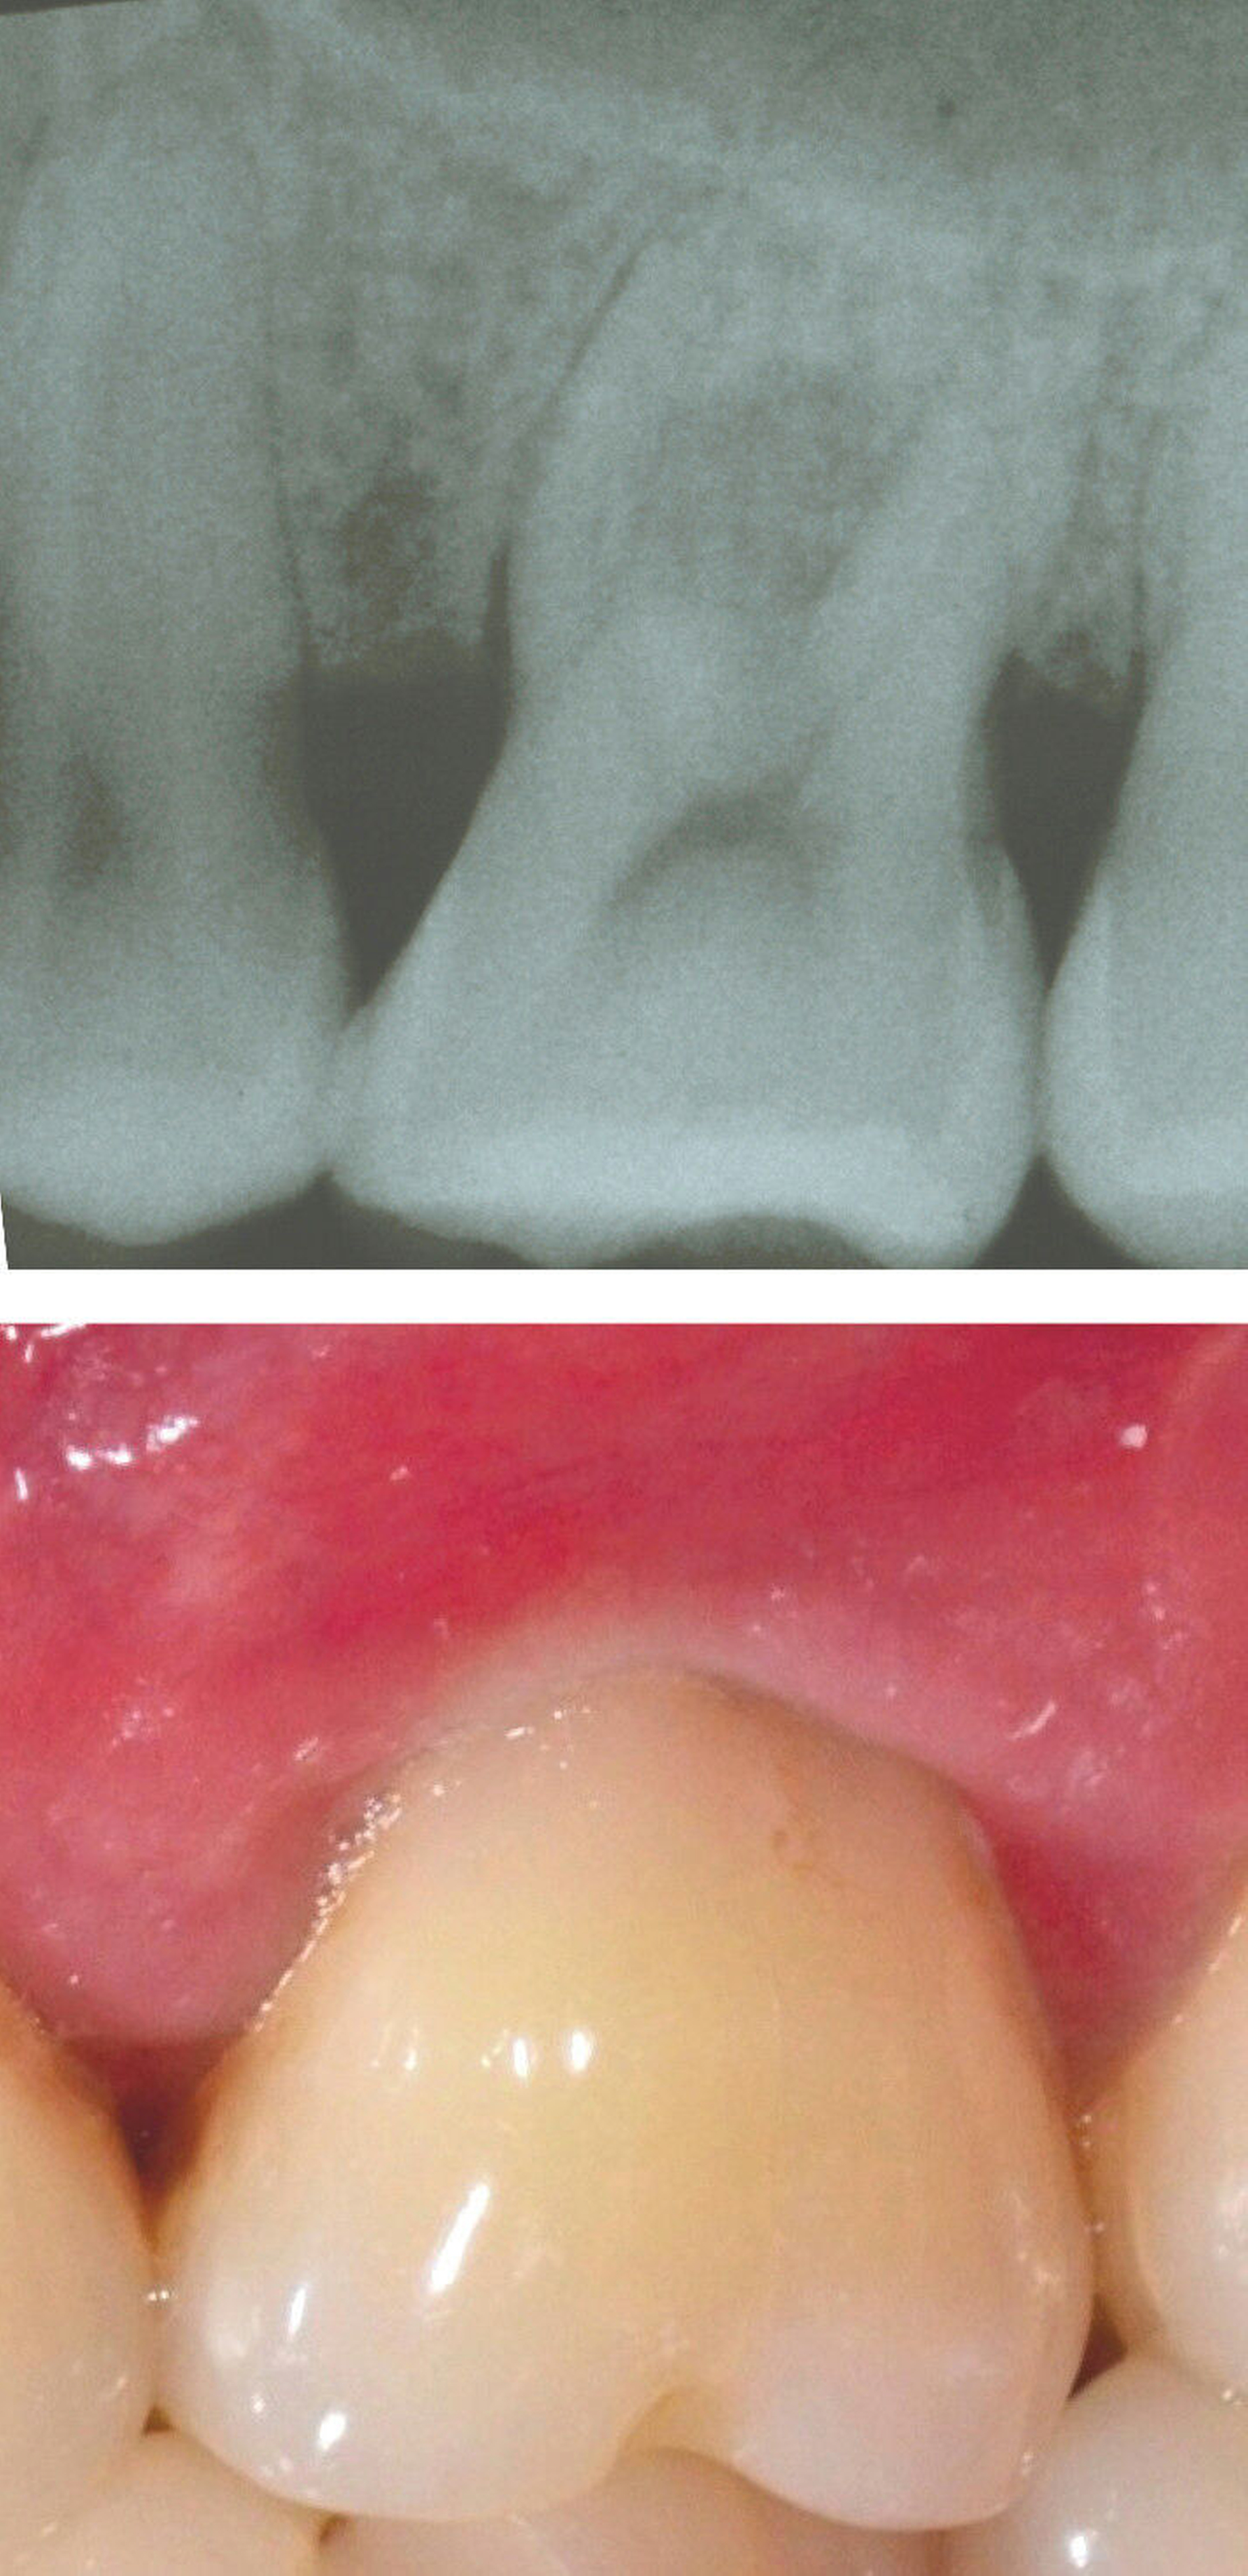

Evidenz aus humaner Histologie

Exemplarische humane Histologie ist der ultimative Beweis für ein regeneratives Heilungsergebnis und wird benötigt, um die aus klinischen Regenerationsstudien gewonnenen Informationen zu ergänzen [Machtei, 1997]. Der Nachweis einer parodontalen Regeneration erfordert den histologischen Nachweis von wiederhergestellten zahntragenden Geweben, einschließlich Zement, parodontalem Ligament und Alveolarknochen an einer zuvor Plaque-besiedelten Wurzeloberfläche. Obwohl solche Ergebnisse in gut kontrollierten experimentellen Tierstudien für eine Vielzahl von Behandlungsmodalitäten nachgewiesen worden sind, wurde bei der Überprüfung der histologischen Beweise für parodontale Regeneration in Furkationsdefekten festgestellt, dass begrenzte Informationen aus humaner Histologie vorliegen [Laugisch et al., 2019] und zwar für GTR [Gottlow et al., 1986; Stoller et al., 2001] eine Kombination aus GTR und KEM [Harris, 2002] und KEM [Camelo et al., 2003; Nevins et al., 2003].